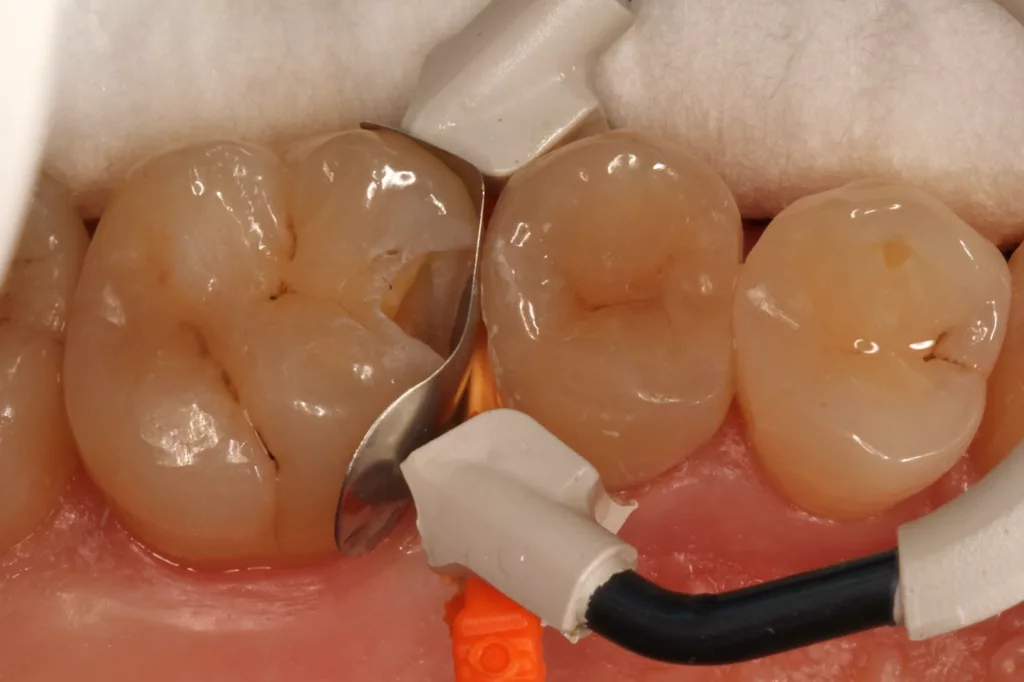

Fall 5: Versorgung einer okklusalen Kavität an einem unteren Molaren

Auch im Molarenbereich können Bulkflow-Materialien effektiv und ökonomisch eingesetzt werden, ohne Abstriche an der Ästhetik machen zu müssen, was der Fall des hier versorgten Zahnes 46 bei einer 22-jährigen Patientin zeigt. Die Abbildung 24 stellt die bereits präparierte und mit einem Einzelzahnkofferdam isolierte Kavität mit der Phosphorsäurekonditionierung der Schmelzränder (Gel Etchant, Kerr) dar. Die Entscheidung zur absoluten Trockenlegung fiel aufgrund der nicht so einfach kontrollierbaren Zunge und der vielen Schluckreflexe, was das Risiko einer ungewollten Speichelkontamination der Klebefläche unverhältnismäßig erhöhte.

Die Verwendung des Kofferdams ist generell eine sehr empfehlenswerte, aber keine zwingende Voraussetzung zur Etablierung einer suffizienten Kontaminationskontrolle [47,96]. Das bisher auch bereits verwendete Zwei-Schritt-Universaladhäsiv G2 Universal wurde hier in der selektiven Schmelzätztechnik angewendet, d.h., das Material arbeitet auf dem Dentin selbstkonditionierend (Abb. 25). Die bislang zu diesem innovativen Mehrflaschen-Universaladhäsiv publizierten Daten zeigen eine beeindruckende Performance, die den Vergleich mit sogenannten Goldstandards [98] wie einem Optibond FL nicht scheuen müssen [13,18,34,58,63,114,119,127,130]. Im nächsten Schritt wurden die einzelnen Höcker mit dem angenehm standfesten Flowable aufgebaut (Abb. 26). Die Abbildung 27 zeigt die komplett versorgte okklusale Kavität, die Abbildung 28 die Situation unmittelbar nach Ausarbeitung und Politur. Erneut beeindruckt die gute Farbadaptation.